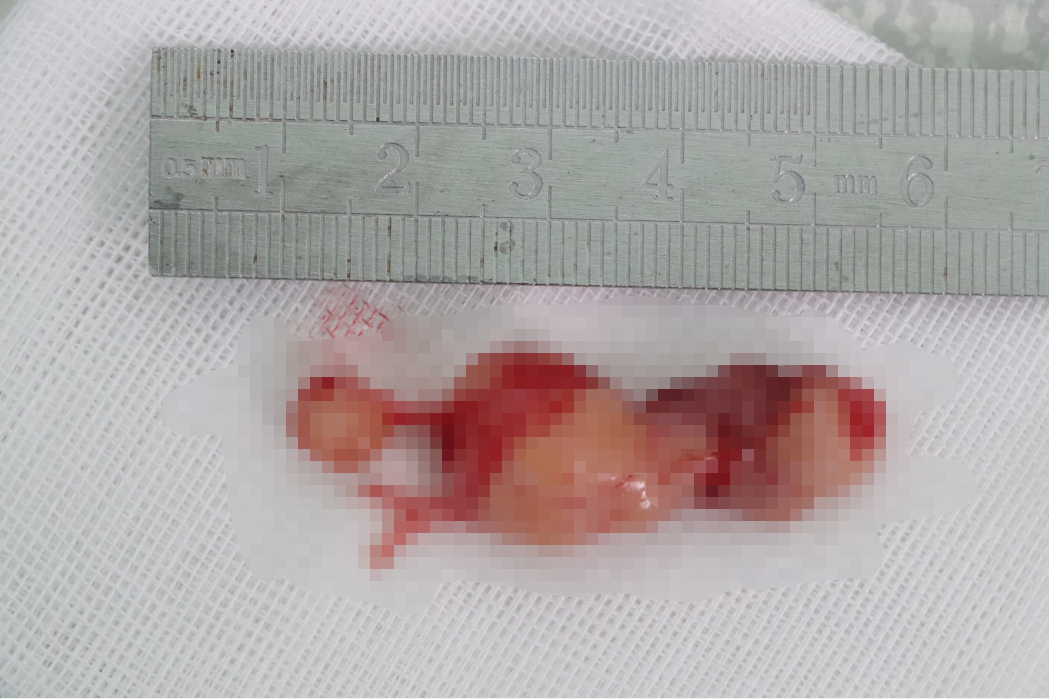

7月1日,温州医科大学附属眼视光医院院长吴文灿教授携手温州医科大学附属第一医院神经外科副主任医师夏雷,10多名医护人员鏖战8个多小时,从眼眶里“揪出”一个“小老鼠般”大小的肿瘤,长达4.5厘米。这个高难度的手术解除了患者20余年的痛苦,在国内外尚未见此类报道。

手术取出的肿瘤,长达4.5厘米。